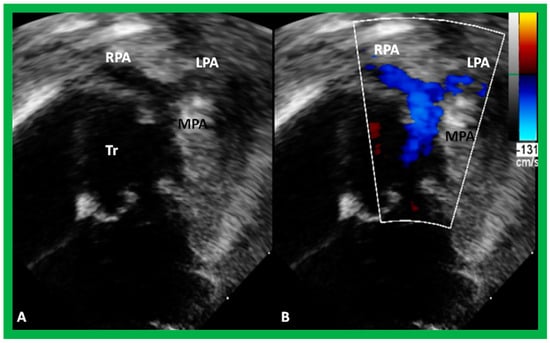

Other ventriculo-arterial connection abnormalities are only one great vessel arising for the ventricles, i.e., truncus arteriosus (Figure 50), and atresia of one of the semilunar valves/great vessels, namely pulmonary and aortic atresia. As reviewed for the other anomalies in the preceding sections, these cardiac anomalies can also be defined by echocardiography with an infrequent necessity for other imaging tools, namely, MRI, CT, and angiography.

Figure 50. Selected echo frames from modified apical four-chamber views demonstrating the origin of one great vessel, truncus arteriosus (Tr), from the heart. Two dimensional (A) and color flow (B) frames demonstrating the origin of the main pulmonary artery (MPA) from the left of the Tr bifurcating into the right (RPA) and left (LPA) pulmonary arteries are shown. Replicated from reference [44].